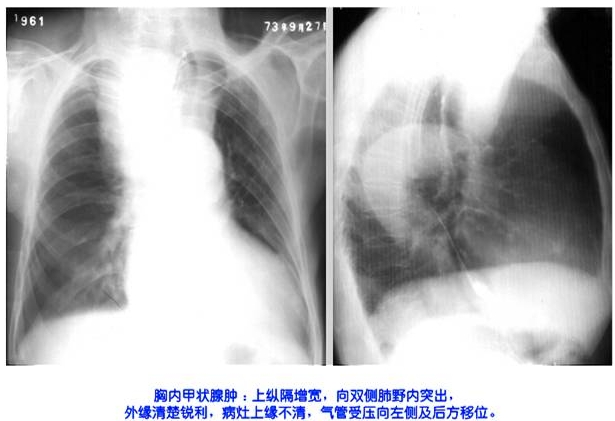

照片名称:熊内甲状腺肿